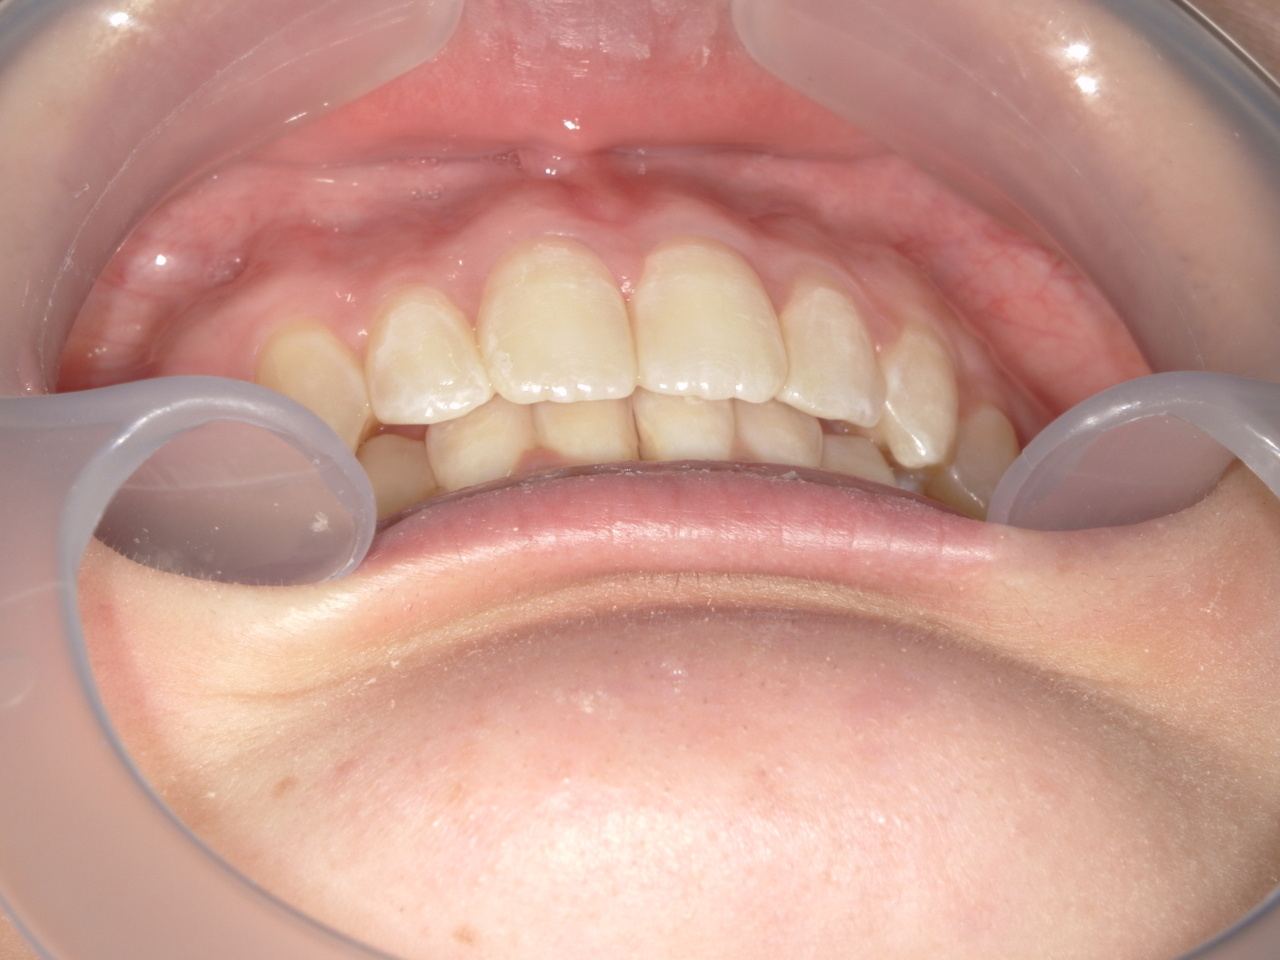

治療前

治療説明 歯科矯正でも目立ちにくい矯正方法であるマウスピース矯正で治療しました

治療期間 2年1か月

治療費用49,8000 円

治療後

治療の副作用(リスク)歯の動き方には個人差があり、予想された治療期間が延長する可能性があります。。マウスピースの使用状況、矯正歯科治療には患者さんの協力が必要であり、それらが治療結果や治療期間に影響します